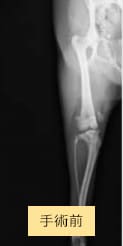

症例2

チワワ×マルチーズ(4歳10ヶ月齢、雌)

グレードⅡ〜Ⅲ 外科手術

- 【初診時症状】

- 他院にて両後肢パテラグレードⅢと診断。手術を希望されて受診

- 【手術】

- 滑車溝形成術、脛骨粗面転位術、関節包縫縮を実施

- 【経過】

- 性格的にご自宅での安静が難しいため、術後2週間入院。術後4週間で屋内での運動制限を徐々に解除、8週間でお散歩の距離を少しずつ伸ばしていくも問題なし。 現在は制限なく生活